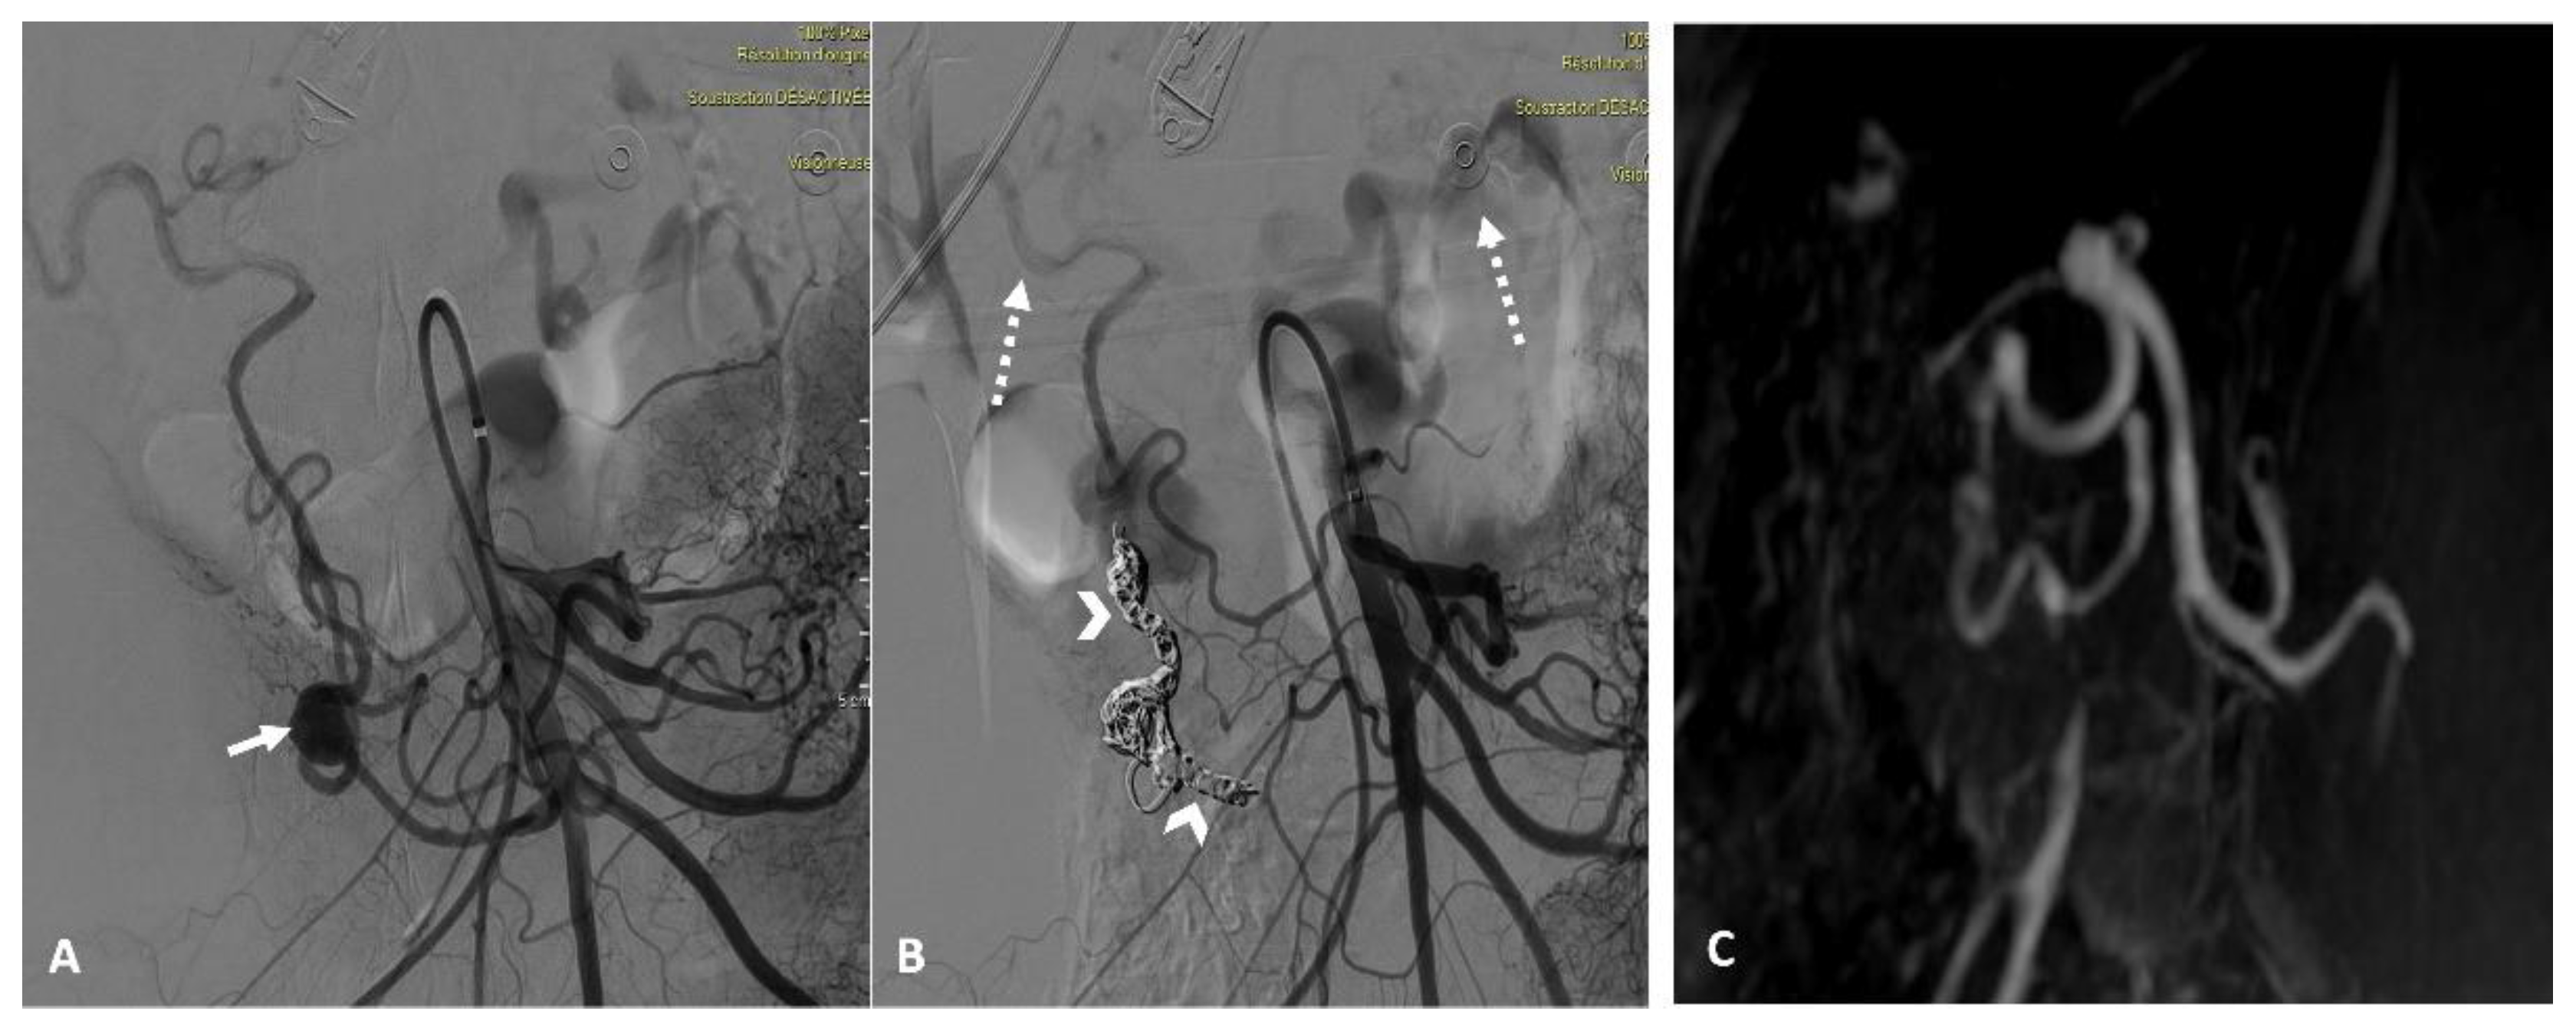

Figure 1. Abdominal CT after contrast injection at the arterial phase, in a coronal view with maximum-intensity-projection reformatting (A), oblique 3D volume rendering (B), and sagittal 3D volume rendering (C) reconstructions showing a tight stenosis at the origin of the celiac trunk due to compression by the median arcuate ligament (solid arrow, C) and an unruptured aneurysm of the pancreaticoduodenal arcade (dashed arrow, A/B/C), as well as aneurysm’s inflow and outflow tracts (arrowhead, A/B).

All patients underwent an abdominal dynamic contrast-enhanced CT scan using a multi-detector row CT (MDCT) (Revolution CT 256; GE Healthcare, Waukesha - WI, USA or Somatom Definition AS+128; Siemens Healthineers, Erlangen - Germany). The imaging protocol included unenhanced, arterial, and portal phase acquisitions following the intravenous administration of 1.5 mL/kg of iodinated contrast agent (Iomeron, 350-Iomeprol; Bracco Imaging, Milan, Italy) at a rate of 3–4 mL/s. A bolus-tracking technique with automated scan triggering was used, placing an elliptic region of interest in the descending thoracic aorta at the diaphragm level, with an enhancement threshold set at 100 HU. CT acquisition and reconstruction settings included: a tube current range of 150–650 mA (mean: 455), a tube voltage of 120 kVp, a rotation time of 0.7 s, and a pitch of 1.375. Automatic exposure control was managed using Auto mA-Smart mA with a noise index of 25, and the field of view was set to large body. Using model-based iterative reconstruction, images were reconstructed with a standard reconstruction kernel at a section thickness of 0.625 mm. The reconstructed images were archived in the institutional picture archiving and communication system (PACS) (Figure 1).